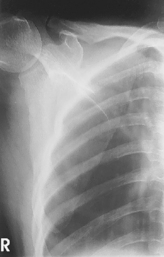

AP trauma projection (neutral rotation) (S)

Important for humerus and shoulder projections: Do not attempt to rotate upper limb if fracture or dislocation is suspected without special orders by a physician.